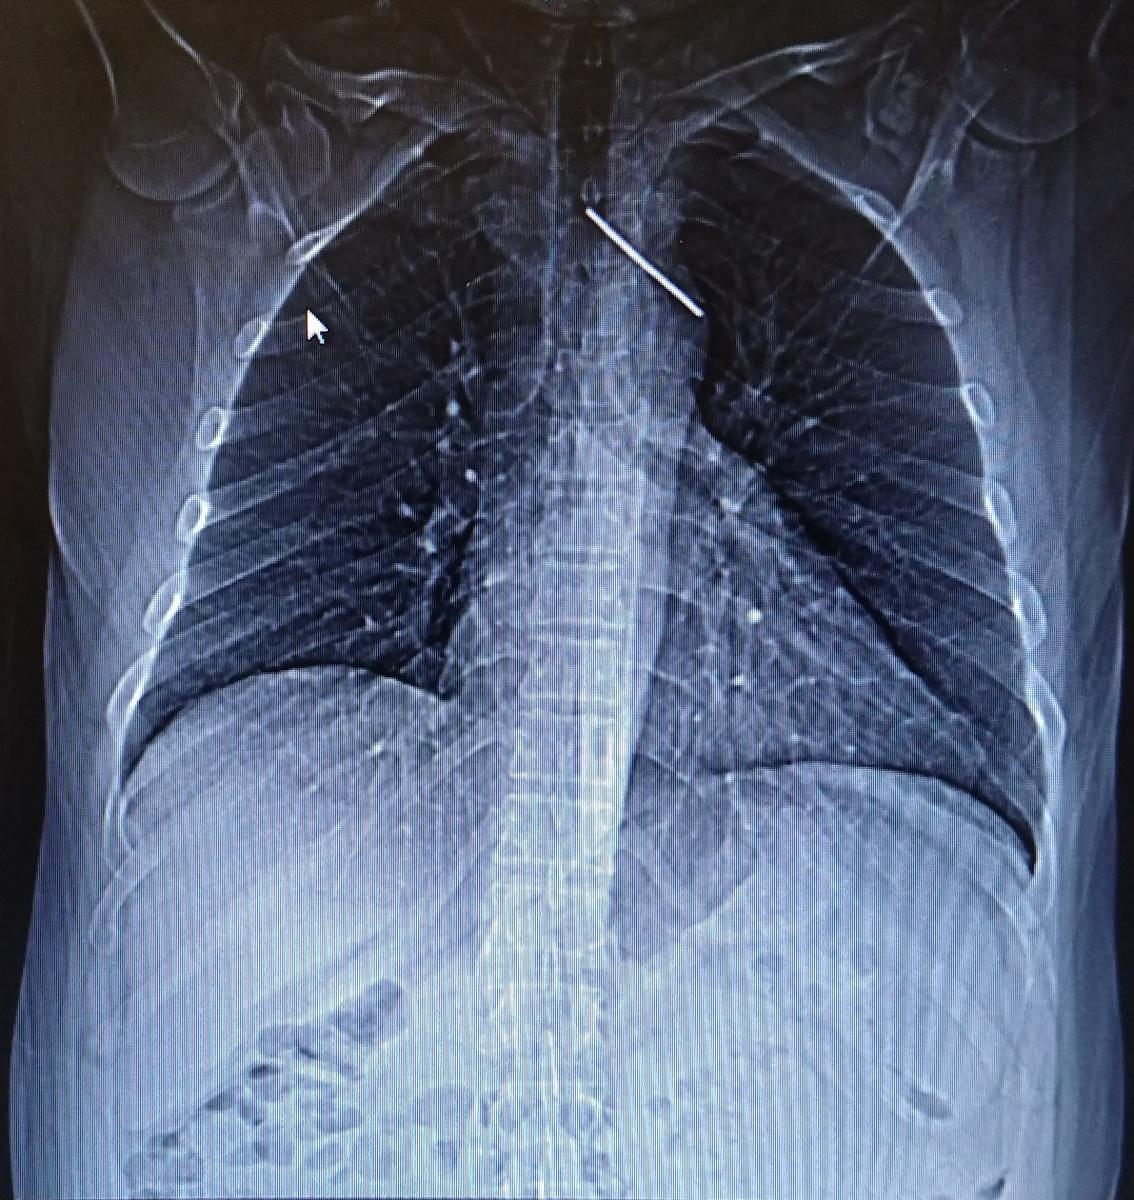

Figure 1. Chest radiograph showing the migrating K-wire, used to fix a right clavicular fracture 34 years previously, in the mediastinum.

An asymptomatic 46-year-old man fell down at his workplace and sought medical consultation because of the accident. In the emergency department, a chest radiograph revealed that a K-wire used to fix a right clavicular fracture 34 years previously had migrated through the anterior mediastinum and into the left upper lobe (Figure 1).